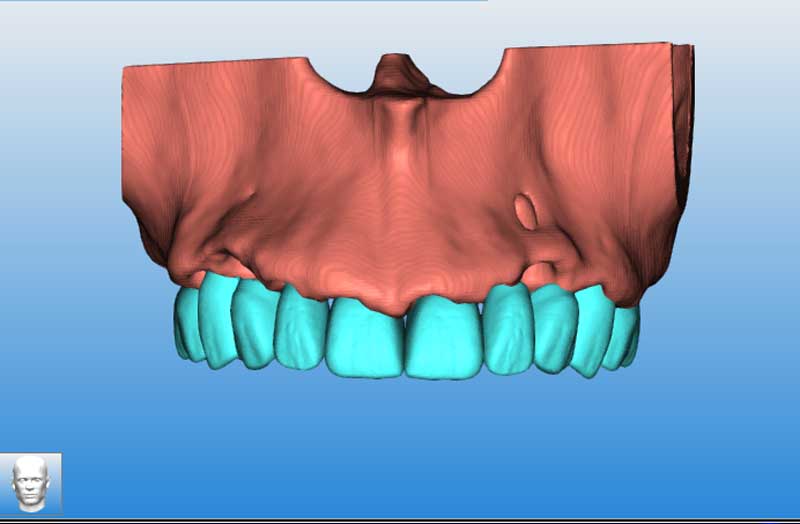

Prova estetica con reperi radiopachi

anatomia

Matching DCM Stl

Matching effettuato

Segmentazione del mascellare, senza i denti

Segmentazione eseguita

Sovrapposizione mockup DCM e Mascellare segmentato 1

Mockup su mascellare segmentato